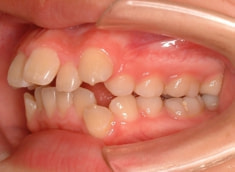

上顎前突ケース

治療法:表の矯正(T21ブラケット)

治療前

治療後(1年2ヶ月後)